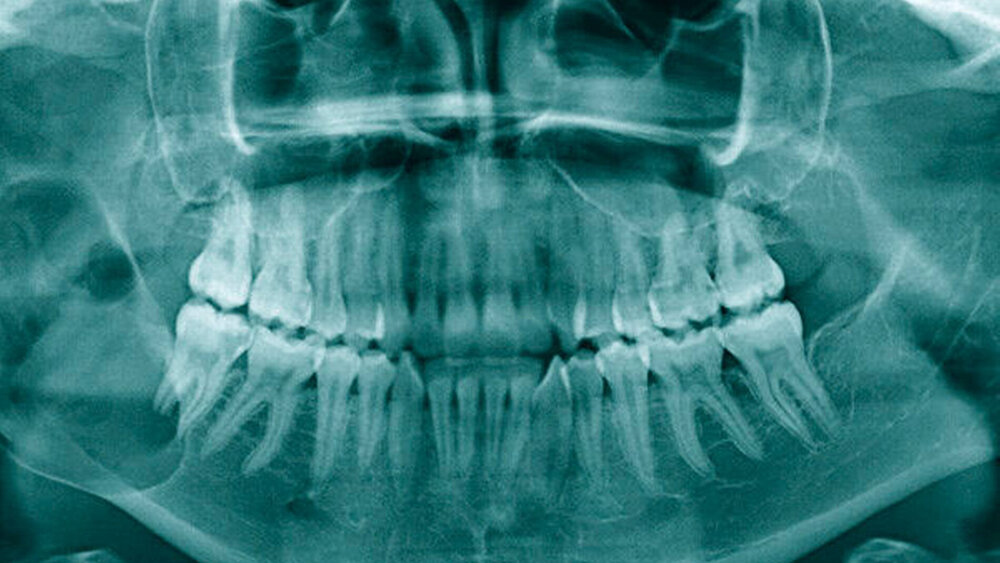

Eine 18-jährige Patientin stellt sich mit einer seit vier Wochen persistierenden Schwellung im Bereich des rechten Unterkiefers bei ihrem Hauszahnarzt vor. In der angefertigten Panoramaschichtaufnahme imponiert eine ausgedehnte und scharf begrenzte Aufhellung, die ausgehend von Regio 47 nahezu den gesamten Ramus mandibulae einnimmt (Abbildung 1). Daraufhin wird die Patientin an die Klinik für Mund-, Kiefer- und Gesichtschirurgie der Universitätsmedizin Mainz überwiesen, wo sich klinisch zusätzlich bereits eine ausgeprägte Mundbodenschwellung darstellt. Der Zahn 47 zeigt sich perkussionsempfindlich; die Vitalitätsproben von 46 und 47 erweisen sich als positiv. Die periphere Durchblutung, Sensibilität und Motorik sind – trotz der nervnahen Lokalisation des Befunds – unauffällig.

Wie im vorliegenden Fall zählen zu den möglichen Symptomen eine schmerzlose Auftreibung des Kiefers – meist in bukkolingualer Richtung – sowie eine Weichgewebsinvasion oder Wurzelresorptionen (Abbildung 1) mit konsekutiver Zahnlockerung bis hin zur Malokklusion [Schneider und Kämmerer, 2019]. Hyp- oder Parästhesien werden im Zusammenhang mit Ameloblastomen als eher untypisch beschrieben [McClary et al., 2016]. Radiologisch erscheint das Ameloblastom charakteristischerweise als scharf begrenzte, polyzystische Aufhellung mit häufig seifenblasenartiger Zeichnung. Gelegentlich besteht eine Beziehung zu verlagerten Zähnen oder Wurzelresorptionen.